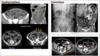

Diskusprolaps og Spinalstenose: - Hvad er forskellen mellem Diskusprolaps (**ve.**) og Spinalstenose (**hø.**)?: **1** - Behandling: **2**

1: **Diskusprolaps** (**ve.**): - Symptomerne er ”AKUT” indsættende - Hyppigst lumbal discusprolaps (80%) **Spinalstenose (forsnævring af rygmarvskanalen)** (**hø.**): - Symptomerne er ”LANGSOMT” indsættende - Kardinalsymptom: reduceret gangdistance 2: * Konservativ behandling: fysioterapi, smertelindrende medicin * Operation: ved manglende effekt